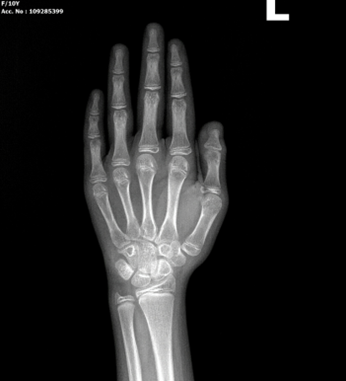

📸 X-quang bàn tay trái: "Cửa sổ" nhìn vào tuổi xương

Trong y học, bàn tay và cổ tay trái là khu vực tập trung nhiều xương nhỏ và các sụn tăng trưởng. Hình ảnh X-quang tại đây phản ánh chân thực Tuổi xương (Bone Age) – thước đo chính xác mức độ trưởng thành sinh học của cơ thể, thay vì chỉ dựa vào Tuổi thực (tuổi theo năm sinh).

Theo tiêu chuẩn quốc tế (phương pháp Greulich & Pyle), bàn tay trái ít bị tác động bởi các hoạt động thuận tay, giúp hình ảnh mang tính khách quan và ổn định hơn trong việc so sánh với biểu đồ chuẩn.

Hình ảnh trẻ nữ 10 tuổi có hình ảnh tuổi xương trên Xquang bàn tay trái tương đương trẻ nữ 11-12 tuổi